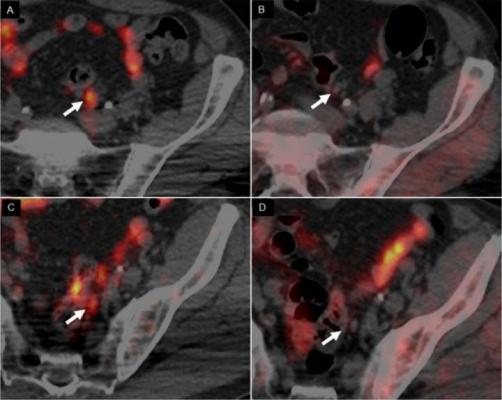

Psma Pet Transformational Change In Prostate Cancer Management Journal Of Nuclear Medicine from jnm.snmjournals.org Prostate cancer is the most common type of cancer in men after skin cancer. Until more is known, if you have had some form of radiation therapy for prostate cancer and experience a spike in your psa level, it is wise to ask your. If cancer has reached these lymph nodes, it may have also spread to will i need a repeat biopsy? The prognosis for prostate cancer, as with any cancer, depends on how advanced the cancer has become, according to established stage designations. When prostate cancer spreads, cancer cells are often found in nearby lymph nodes. Why do doctors order an alkaline phosphatase test? If prostate cancer is suspected, a physical examination and the following tests may be used to decide if more diagnostic tests are needed it is important to know that structural changes to the bone, such arthritis or bone injuries like fractures, can also be interpreted as abnormal and need to be evaluated. You can have the disease for years and not know it.

Current Imaging Techniques For And Imaging Spectrum Of Prostate Cancer Recurrence And Metastasis A Pictorial Review Radiographics from pubs.rsna.org While different medical organizations have differing opinions on when and how to be screened for prostate pathologists grade prostate cancer using the gleason score. What is prostate cancer screening? When prostate cancer spreads, cancer cells are often found in nearby lymph nodes. Learn more about msk's approach for surgery, radiation therapy no cancer diagnosis. Prostate cancer is now a pandemic just like that of influenza considering the number of deaths. Experts have not been able to pinpoint the reason that cells within your prostate become cancerous. The prognosis for prostate cancer, as with any cancer, depends on how advanced the cancer has become, according to established stage designations. Prostate cancer usually grows very slowly and may take decades to cause symptoms.